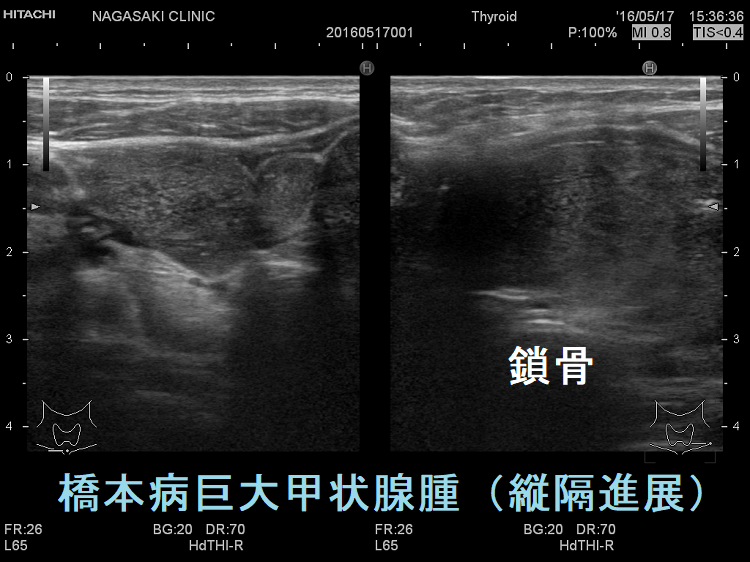

ケース② 橋本病甲状腺腫縦隔進展

ケース③ 橋本病の巨大甲状腺腫が気管圧排